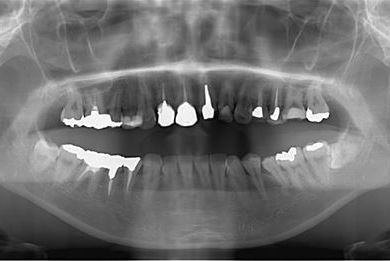

| 性別/年齢 | 女性 / 27歳 | ||||||||||||||||||||||||||||||||

| 主訴 | 審美歯科治療を希望。歯ならびもできるかぎりそろえたい。 | ||||||||||||||||||||||||||||||||

| 治療内容 | オールセラミック4本(オールセラミック用土台4本)、メタルボンドセラミック2本(メタルボンドセラミック用土台2本) | ||||||||||||||||||||||||||||||||

| 総治療費 | 867,825円 | ||||||||||||||||||||||||||||||||

| 治療期間 | 5ヶ月 |

インプラント埋め込み施術は外科治療のため、腫れる可能性があります。また、細菌感染すると施術のやり直しになる場合がありますが、当院では洗浄・滅菌を徹底して感染リスクを抑えます。インプラント周囲炎にならないよう、丁寧な歯磨きが必要です。